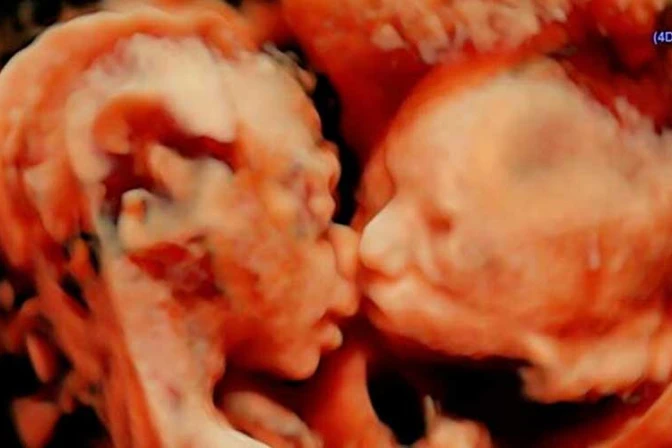

Una mujer estadounidense con 25 semanas de embarazo descubrió algo curioso cuando fue a realizarse una ecografía: vio a sus dos gemelas dándose un tierno beso.

A inicios de abril, Carissa Gill fue con su novio, Randy Good, al centro de ecografías Fetal Vision en Levittown, en el estado de Pensilvania. Ambos se sorprendieron cuando vieron en el ultrasonido que sus primeras hijas, Isabella y Callie, estaban acurrucadas frente a frente y parecía que una de ellas estaba dándole un beso a la otra.

El médico que hizo la ecografía, John Hamburg, expresó al diario The Huffington Post que la imagen es verídica y que "he realizado unas 15 mil de estas, pero nunca había visto a dos gemelos frente a frente como si se besaran. Normalmente la cabeza de uno está arriba y la del otro abajo".

La imagen fue difundida por Fetal Vision a través de su cuenta de Instagram.